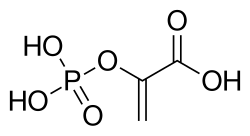

| Phosphoenolpyruvate | |

The level of 2,3-bisphosphoglycerate is elevated: 1,3-bisphosphoglycerate, a precursor of phosphoenolpyruvate which is the substrate for Pyruvate kinase, is increased and so the Luebering-Rapoport pathway is overactivated. This led to a rightward shift in the oxygen dissociation curve of hemoglobin (i.e. it decreases the hemoglobin affinity for oxygen): In consequence, patients may tolerate anemia surprisingly well.[8]

Pyruvate kinase is the last enzyme involved in the glycolytic process, transferring the phosphate group from phosphenol pyruvate to a waiting adenosine diphosphate (ADP) molecule, resulting in both adenosine triphosphate (ATP) and pyruvate. This is the second ATP producing step of the process and the third regulatory reaction.[7][12] Pyruvate kinase deficiency in the red blood cells results in an inadequate amount of or complete lack of the enzyme, blocking the completion of the glycolytic pathway. Therefore, all products past the block would be deficient in the red blood cell. These products include ATP and pyruvate.[2]